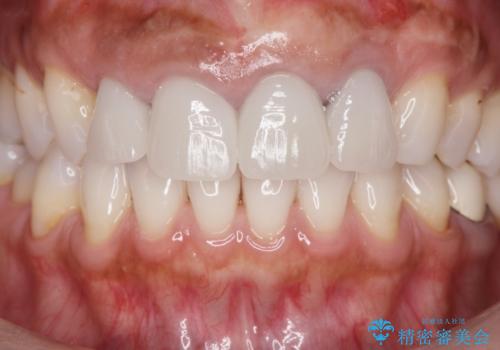

歯槽堤保存術を併用したブリッジ治療

- 前歯がグラグラし、においもする、とのことで改善を求めて来院されました。

一見して問題ないように見える左側の2前歯は、セラミックを除去してみると亀裂や虫歯の再発が見られました。

抜歯時に可及的に歯肉のボリュームを保つよう骨充填材とコラーゲン製剤による填塞を行い審美的かつ機能的なブリッジとなるよう治療を進めます。

- 66万円(ジルコニアクラウン×5・仮歯×5)費用は治療当時の料金となります

一件綺麗に見えるセラミックも適合や精度が悪いと、内部で虫歯が進行し亀裂や破折、悪臭の原因となることがあります。